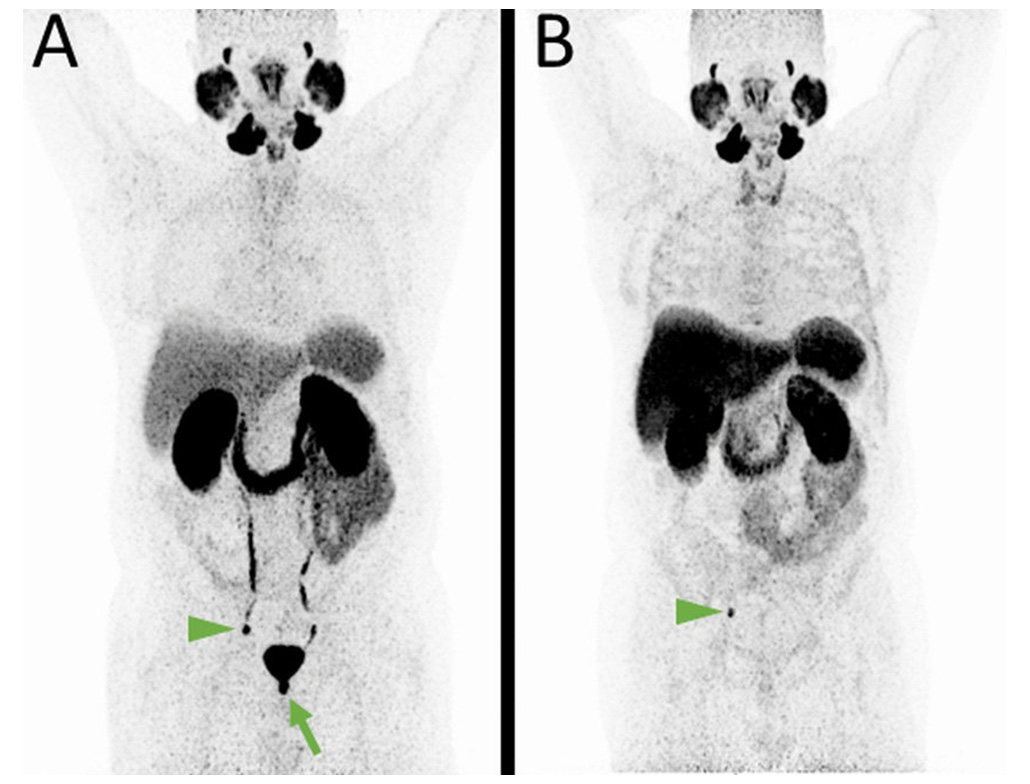

01. 18F‑FDG

Maps glucose metabolism to help find and monitor cancers; also used in heart viability and certain brain conditions for functional assessment.